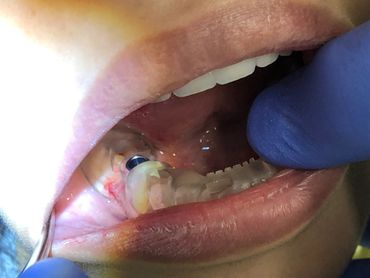

The Neodent GM Guided Surgery Kit is a compact, easy to use guided surgery system. Clinicians can provide CT scan, digital photos, and impressions to a laboratory for precise implant guide fabrication. Temporary teeth can be made and the lab will know the depth, angle, and timing of the connection of the implant. This allows you better esthetics and provides the patient teeth the same day with less chair time.